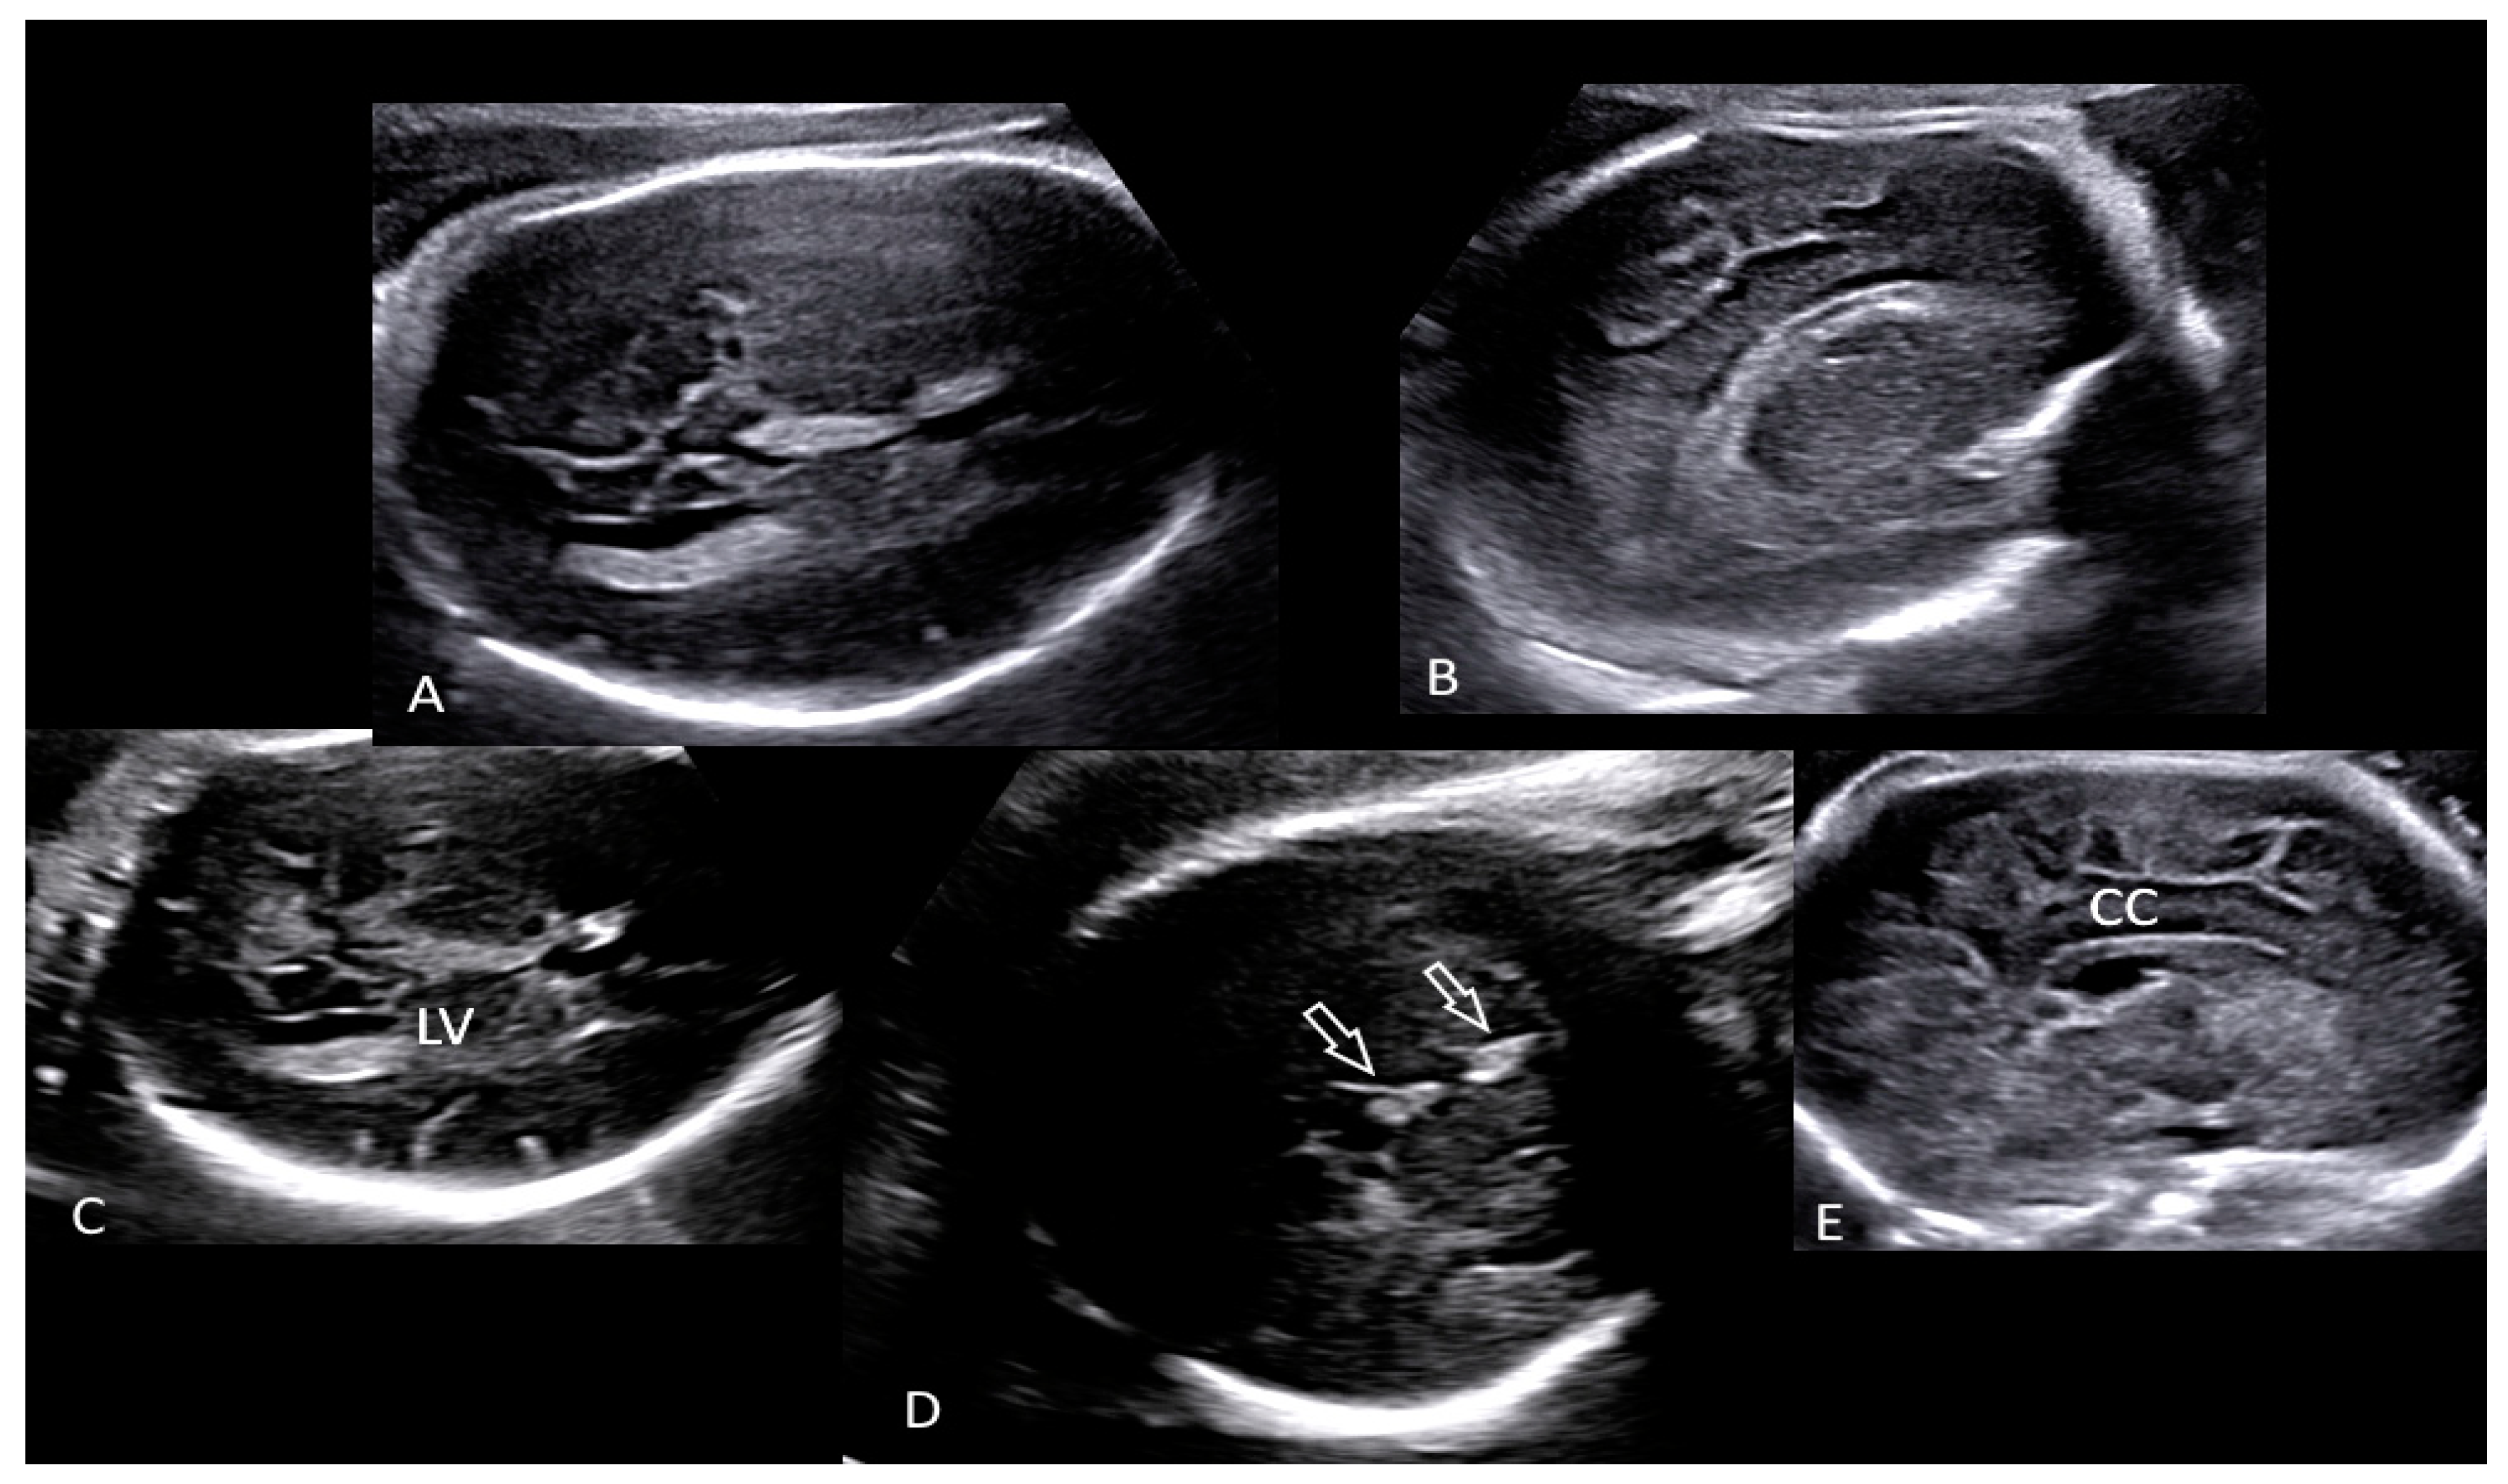

2. The Case